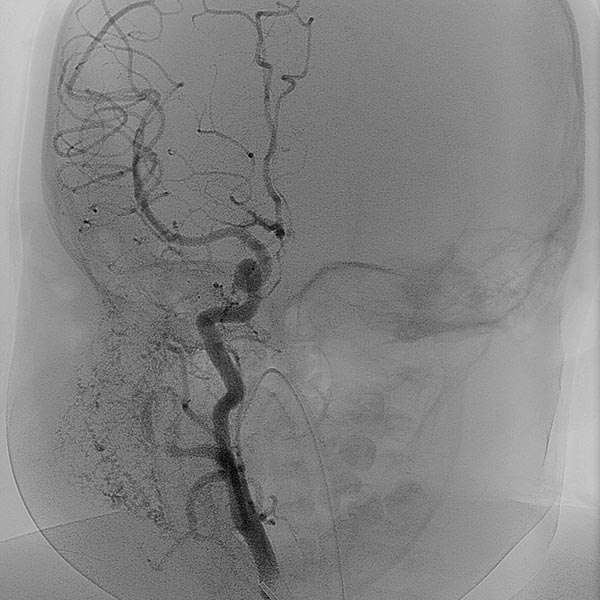

In der digitalen Subtraktionsangiographie (DSA) nach Injektion in die rechte Arteria carotis communis zeigt sich das Hämangiom wie erwartet vor allem aus der Arteria carotis externa versorgt.

Digitale Subtraktionsangiographie (DSA): Nach Einbringen transarteriell eines Führungskatheters 4F in die Arteria carotis externa und Vorbringen eines Mikrokatheters in die Arteria maxillaris. Das Hämangiom zeigt sich als typisches KM-Pooling (Tumorblush). Gut zu sehen auch der transvenös eingebrachte Ballon, der den venösen Abstrom ausblockt. Hier wird jetzt mit Partikeln der Größe 150 Mikron embolisiert ohne dass diese Partikel venös abströmen können.